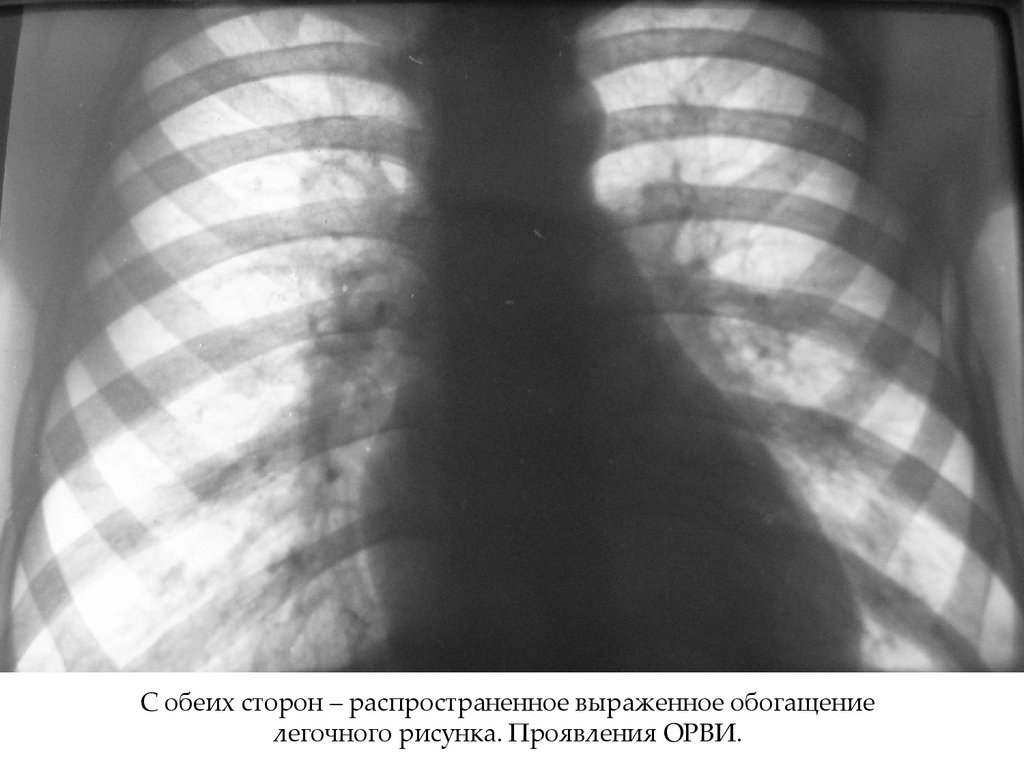

С обеих сторон – распространенное выраженное обогащение

легочного рисунка. Проявления ОРВИ.